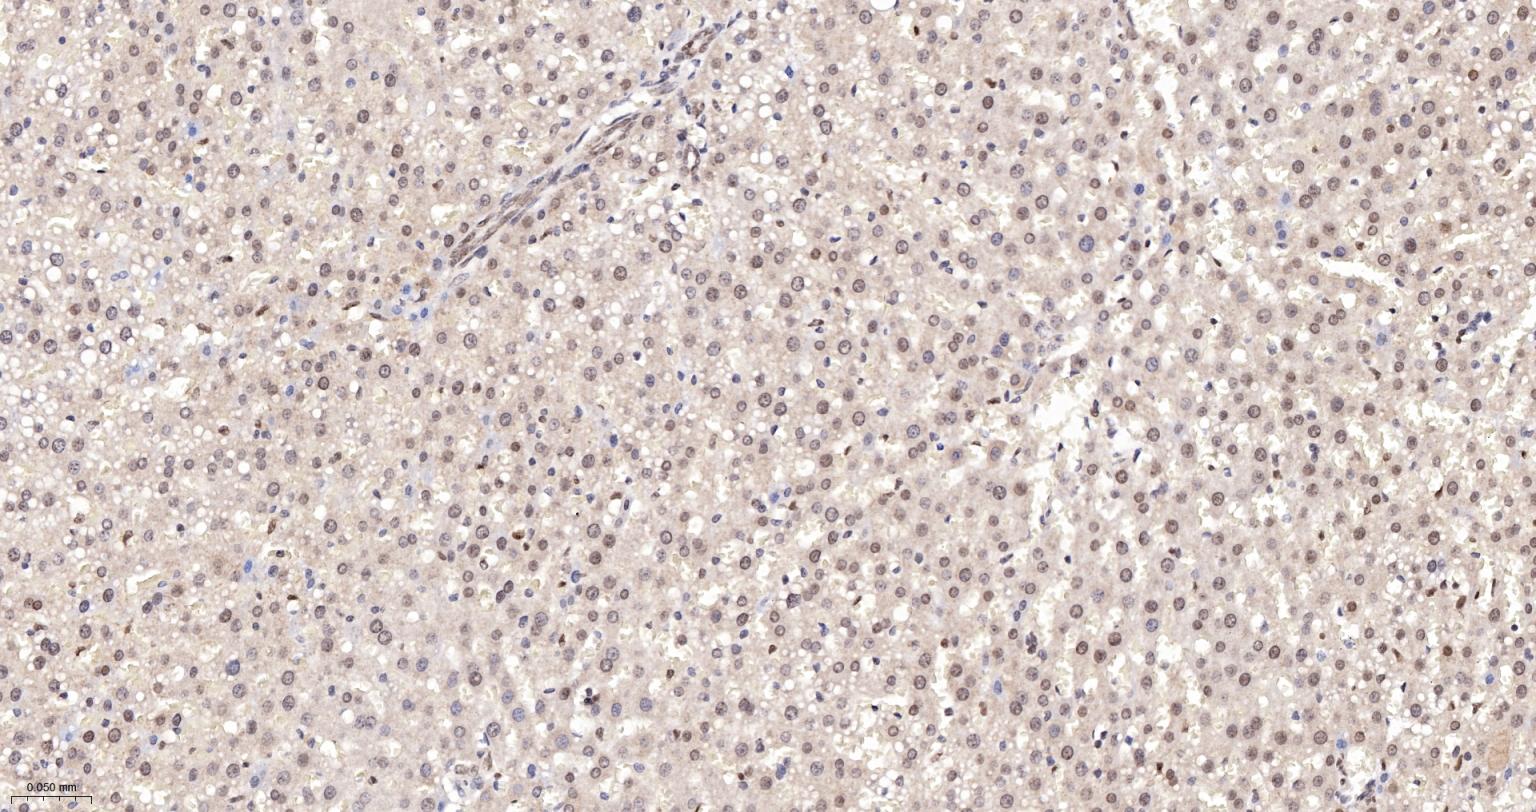

Paraformaldehyde-fixed, paraffin embedded Human Liver; Antigen retrieval by boiling in sodium citrate buffer (pH6.0) for 15 min; The section was incubated with APEX1 Monoclonal Antibody, Unconjugated (bsm-60707R) at 1:200 overnight at 4°C, followed by conjugation to the bs-0295G-HRP and DAB (C-0010) staining.